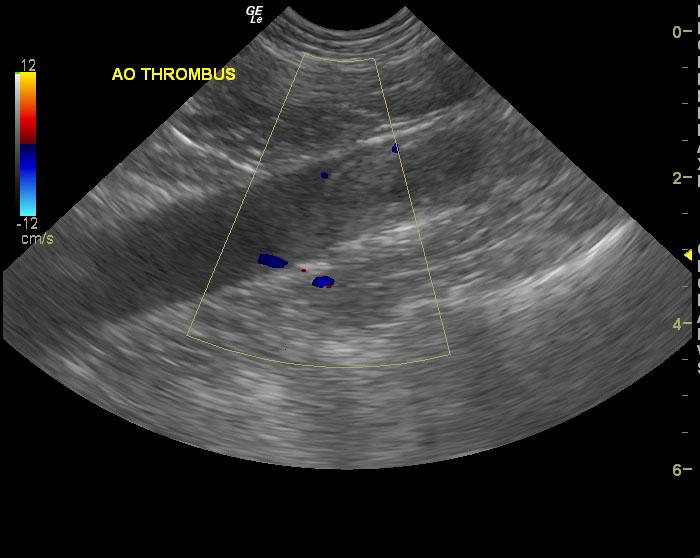

The aorta and left iliac artery were almost completely obstructed by a 6 x 2 cm echogenic thrombus that appeared to be entering into the right iliac artery. The cause of the thrombus could not be ascertained.

Aortic and iliac thrombus. Suspect sepsis or infectious disease. Full coagulation panel, Plavix therapy, Doxycycline and Clindamycin combination would be recommended. Prognosis is extremely guarded. Recheck sonogram in 5-7 days.